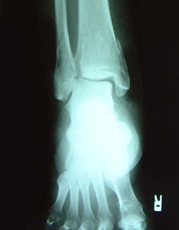

X線所見:脛骨は正面像で下端部の骨折が認められ、末梢骨片は後外方へ転位していた。中枢骨片は側面像で前下方への転位を認めた。腓骨は下端部で斜骨折を認めるが、転位は認めなかった。

初診時の写真・X線

スライドの写真は初診時の外観で内出血の様子

レントゲンの矢印が骨折線を示す